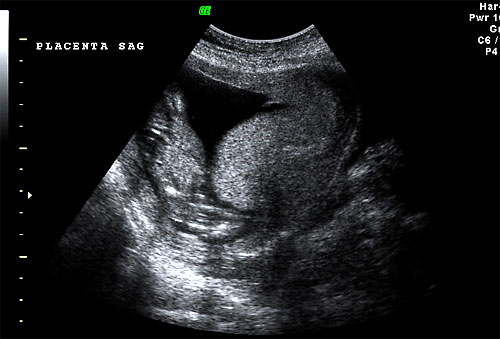

Normal sagittal view of placenta |

Transverse placenta at 16 weeks |